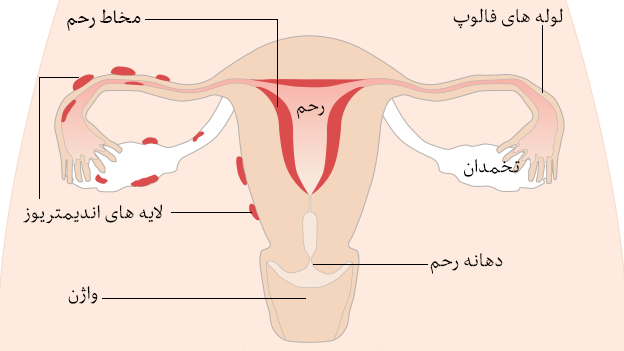

شکل دوم شکم مادری را نشان می دهد که جنین دختر دارد. وحشت مادر از عکس سونوگرافی جنین داخل شکمش عکس. تصاویر جالب از داخل مغز و نخاع انسان آخرین نیوز. بدن انسان کل ساختار انسان است که سر گردن تنه سینه و شکم دو بازو و دست ها و دو ساق پا و پاها را شامل می شود.